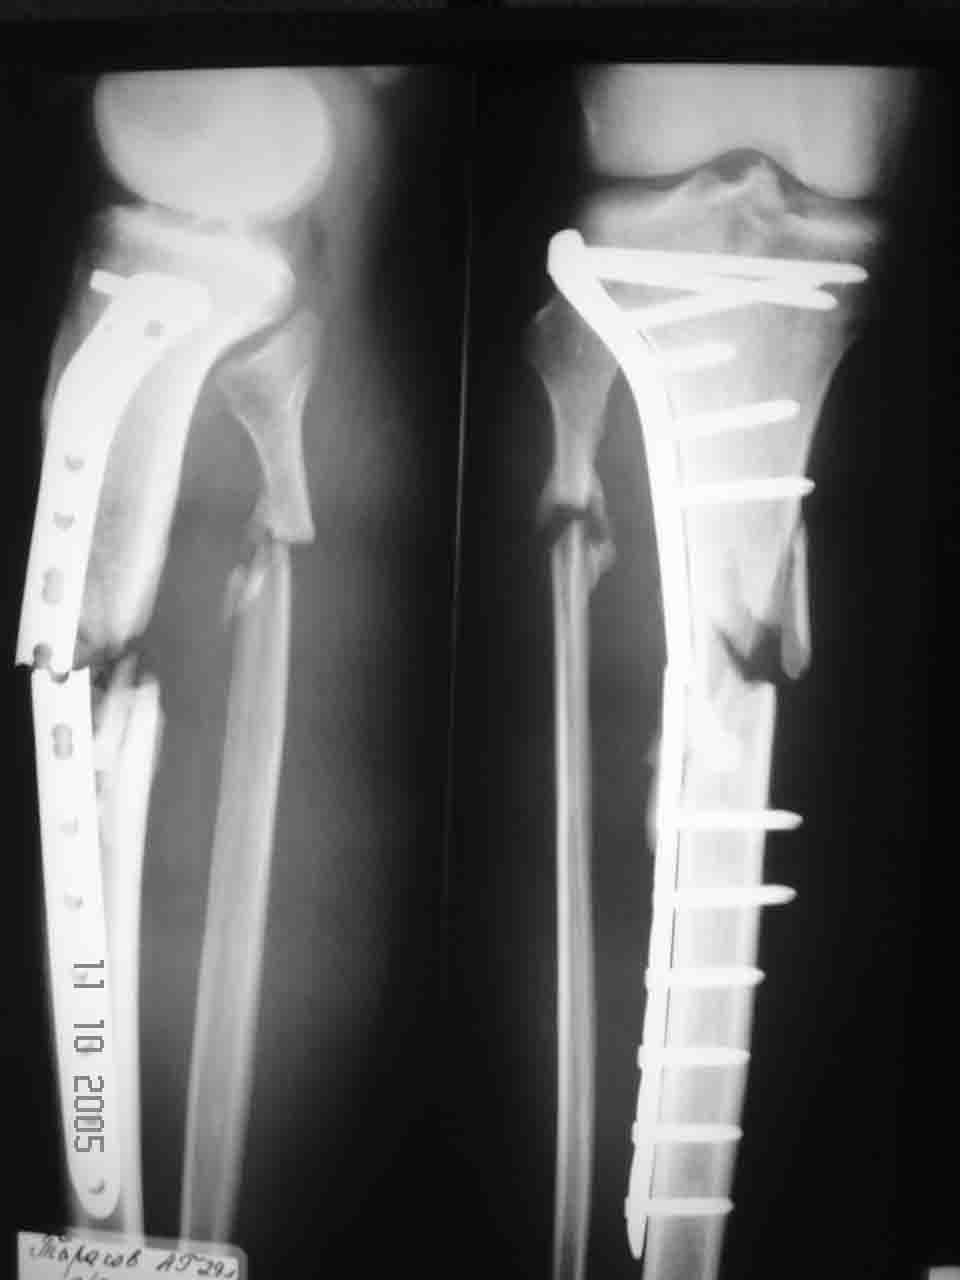

Уважаемый Алексей, глядя на Р-граммы левой голени фиксированной пластиной создается впечатление, что имеется дефект б/берцовой кости. Учитывая это при ЧКО необходимо выполнить костную пластику дефекта. В противном случае кость даже после консолидиции останется слабой, что приведет к повторному перелому. Мне кажется, что в данном случае предпочтителен ЗИО б\берцовой кости с рассверливанием костномозгового канала и блокированием, т.к. при ЗИО активизируются процессы регенерации за счет гематомы в области перелома, что приводит к образованию параоссальной костной мозоли. Плюс к этому в кости будет находится прочный фиксатор, который очень редко ломается и не беспокоит пациента.

Перелом пластины наступил, по нашему мнению, вследствии проведенного нестабильного остеосинтеза (необходимо было выполнить накостный остеосинтез с костной аутопластикой). Возможно проведение данной операции и в настоящее время, то есть при удалении сломанной пластины вновь выполнить стабильный накостный остеосинтез с костной аутопластикой.

Ни в одном, ни в другом случае иммобилизация выбрана неправильно. "на шипе" сращения ждать долго и, извините, глупо. Тем более, что отломки сопоставлены крайне плохо. Иммобилизация и пластиной и стержнем (по рентгенограммам видно)нестабильны. Удалите пластину и интрамедулярную конструкцию и произведите иммобилизацию аппаратами внешней фиксации. Ведь еще Илизаровым доказано, что для голеней лучшей фиксации, чем АВФ нет.

На мой взгляд методы лечения выбраны достаточно грамотно.Ну уж так случилось.На самом деле пластины LCP достаточно коварны хотя сегодня это очень модно.Интрамедулярный синтез повторный здесь врядли хорош.Короткий нестабилный проксимальный фрагмент и если нет серьёзного опыта при данной патологии результата не будет.Я бы опять применил такую же пластину малоинвазивно.Затем разрез по медиальной поверхности,костная пластика и плюс по медиальной стороне реконструктивная пластина.Есть такой опыт и достаточно неплохой.Аппарат не советую.Зависните с ним на год.А пластику открыто все равно надо делать поэтому и медиальная фиксация необходима.И винтов необходимо меньше в LCP.Иначе снова сломается.С уважением.Есть большой матерьял по LCP в том числе и печальный

Причина перелома - на мой взгляд - неадекватная репозиция. Сегмент удлинен, об этом говорит диастаз между отломками малоберцовой кости. Отсюда и впечатление "дефекта". Он есть, но вторичен.